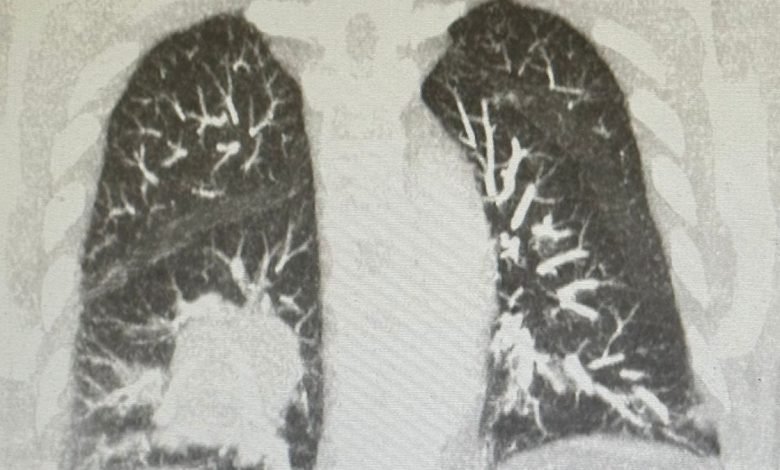

Ο 67χρονος επιχειρηματίας Joe Tippens διαγνώστηκε με καρκίνο του πνεύμονα τον Αύγουστο του 2016. Οι σαρώσεις έδειξαν έναν όγκο στο μέγεθος της γροθιάς του.

Υποβλήθηκε σε χημειοθεραπεία και ακτινοβολία πέντε φορές την εβδομάδα, μετά τις οποίες ο μεγάλος όγκος στον αριστερό πνεύμονά του εξαφανίστηκε. Ο Tippens, ωστόσο, είπε ότι παραλίγο να υποκύψει στις θεραπείες.

Στις αρχές του 2017, έλαβε τρομερά νέα. Ο ογκολόγος του είπε ότι του είχαν απομείνει μόνο λίγοι μήνες ζωής. Ο Tippens είχε μεταστάσεις παντού, συμπεριλαμβανομένου του λαιμού, των οστών και του ήπατος.